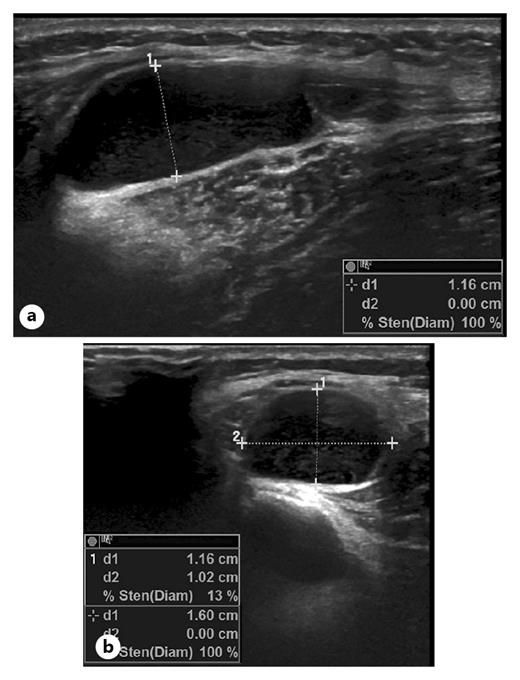

Endovascular Treatment of Cervical Artery Dissection Ten Case Reports Case Reports In Neurology Karger Scilit source title profile of case reports in neurology scilit is a comprehensive content aggregator platform for scholarly publications. We report a very rare case of isolated accessory nerve palsy due to a large thrombosed aneurysm of the intracranial vertebral artery. Published by karger online issn:. Articles from case reports in neurology are provided here courtesy of karger publishers. Case. Case Reports In Neurology Karger.

From karger.com